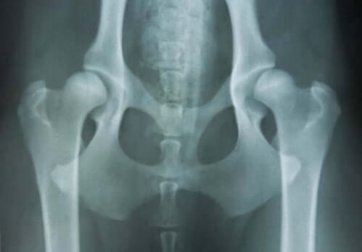

Sem dúvida alguma, o estudo radiológico é essencial para confirmar a enfermidade óssea, e tentar abordar um diagnóstico preciso. Esse processo requer profissionais especializados.

Atualmente há um estudo molecular confirmatório. São as alterações dos genes FGFR3, COL2a1 e SHOX, que dão origem às displasias mais frequentes. Nos últimos anos, maior precisão diagnóstica tem sido acompanhada de maiores oportunidades terapêuticas.